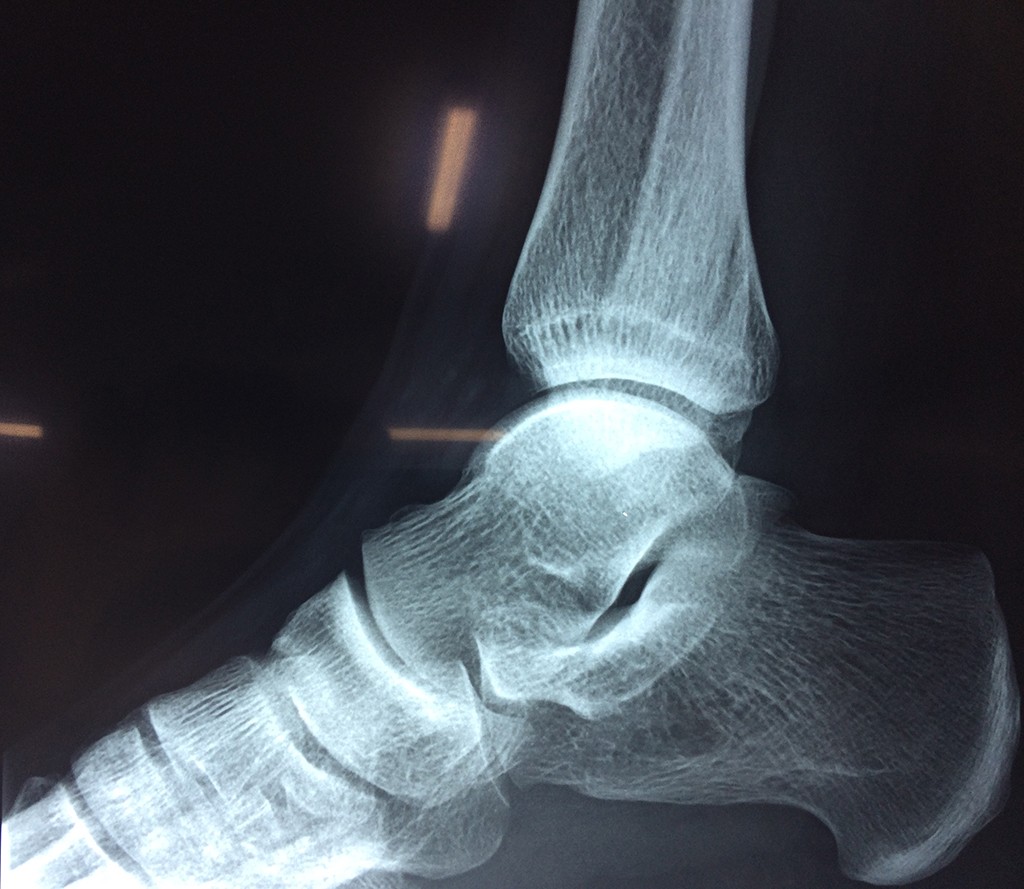

Una fractura de tobillo es la rotura de uno o más de los huesos del tobillo. Estas fracturas pueden ser:

- Los extremos de los huesos están desalineados entre sí (desplazados).

- La fractura se extiende hasta la articulación del tobillo (fractura intra-articular).